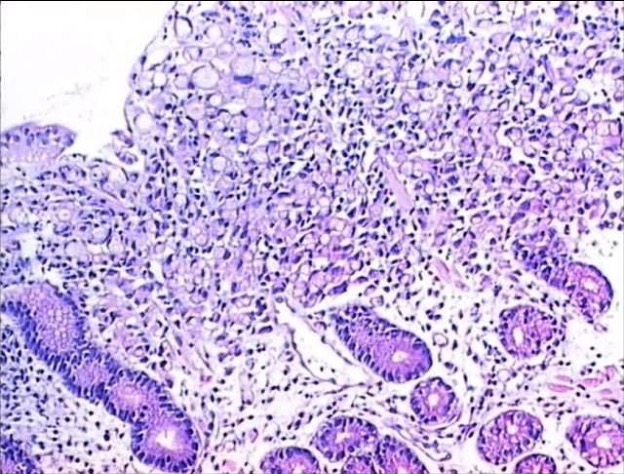

215.慢性支气管炎的病变性质是

慢性非特异性炎症